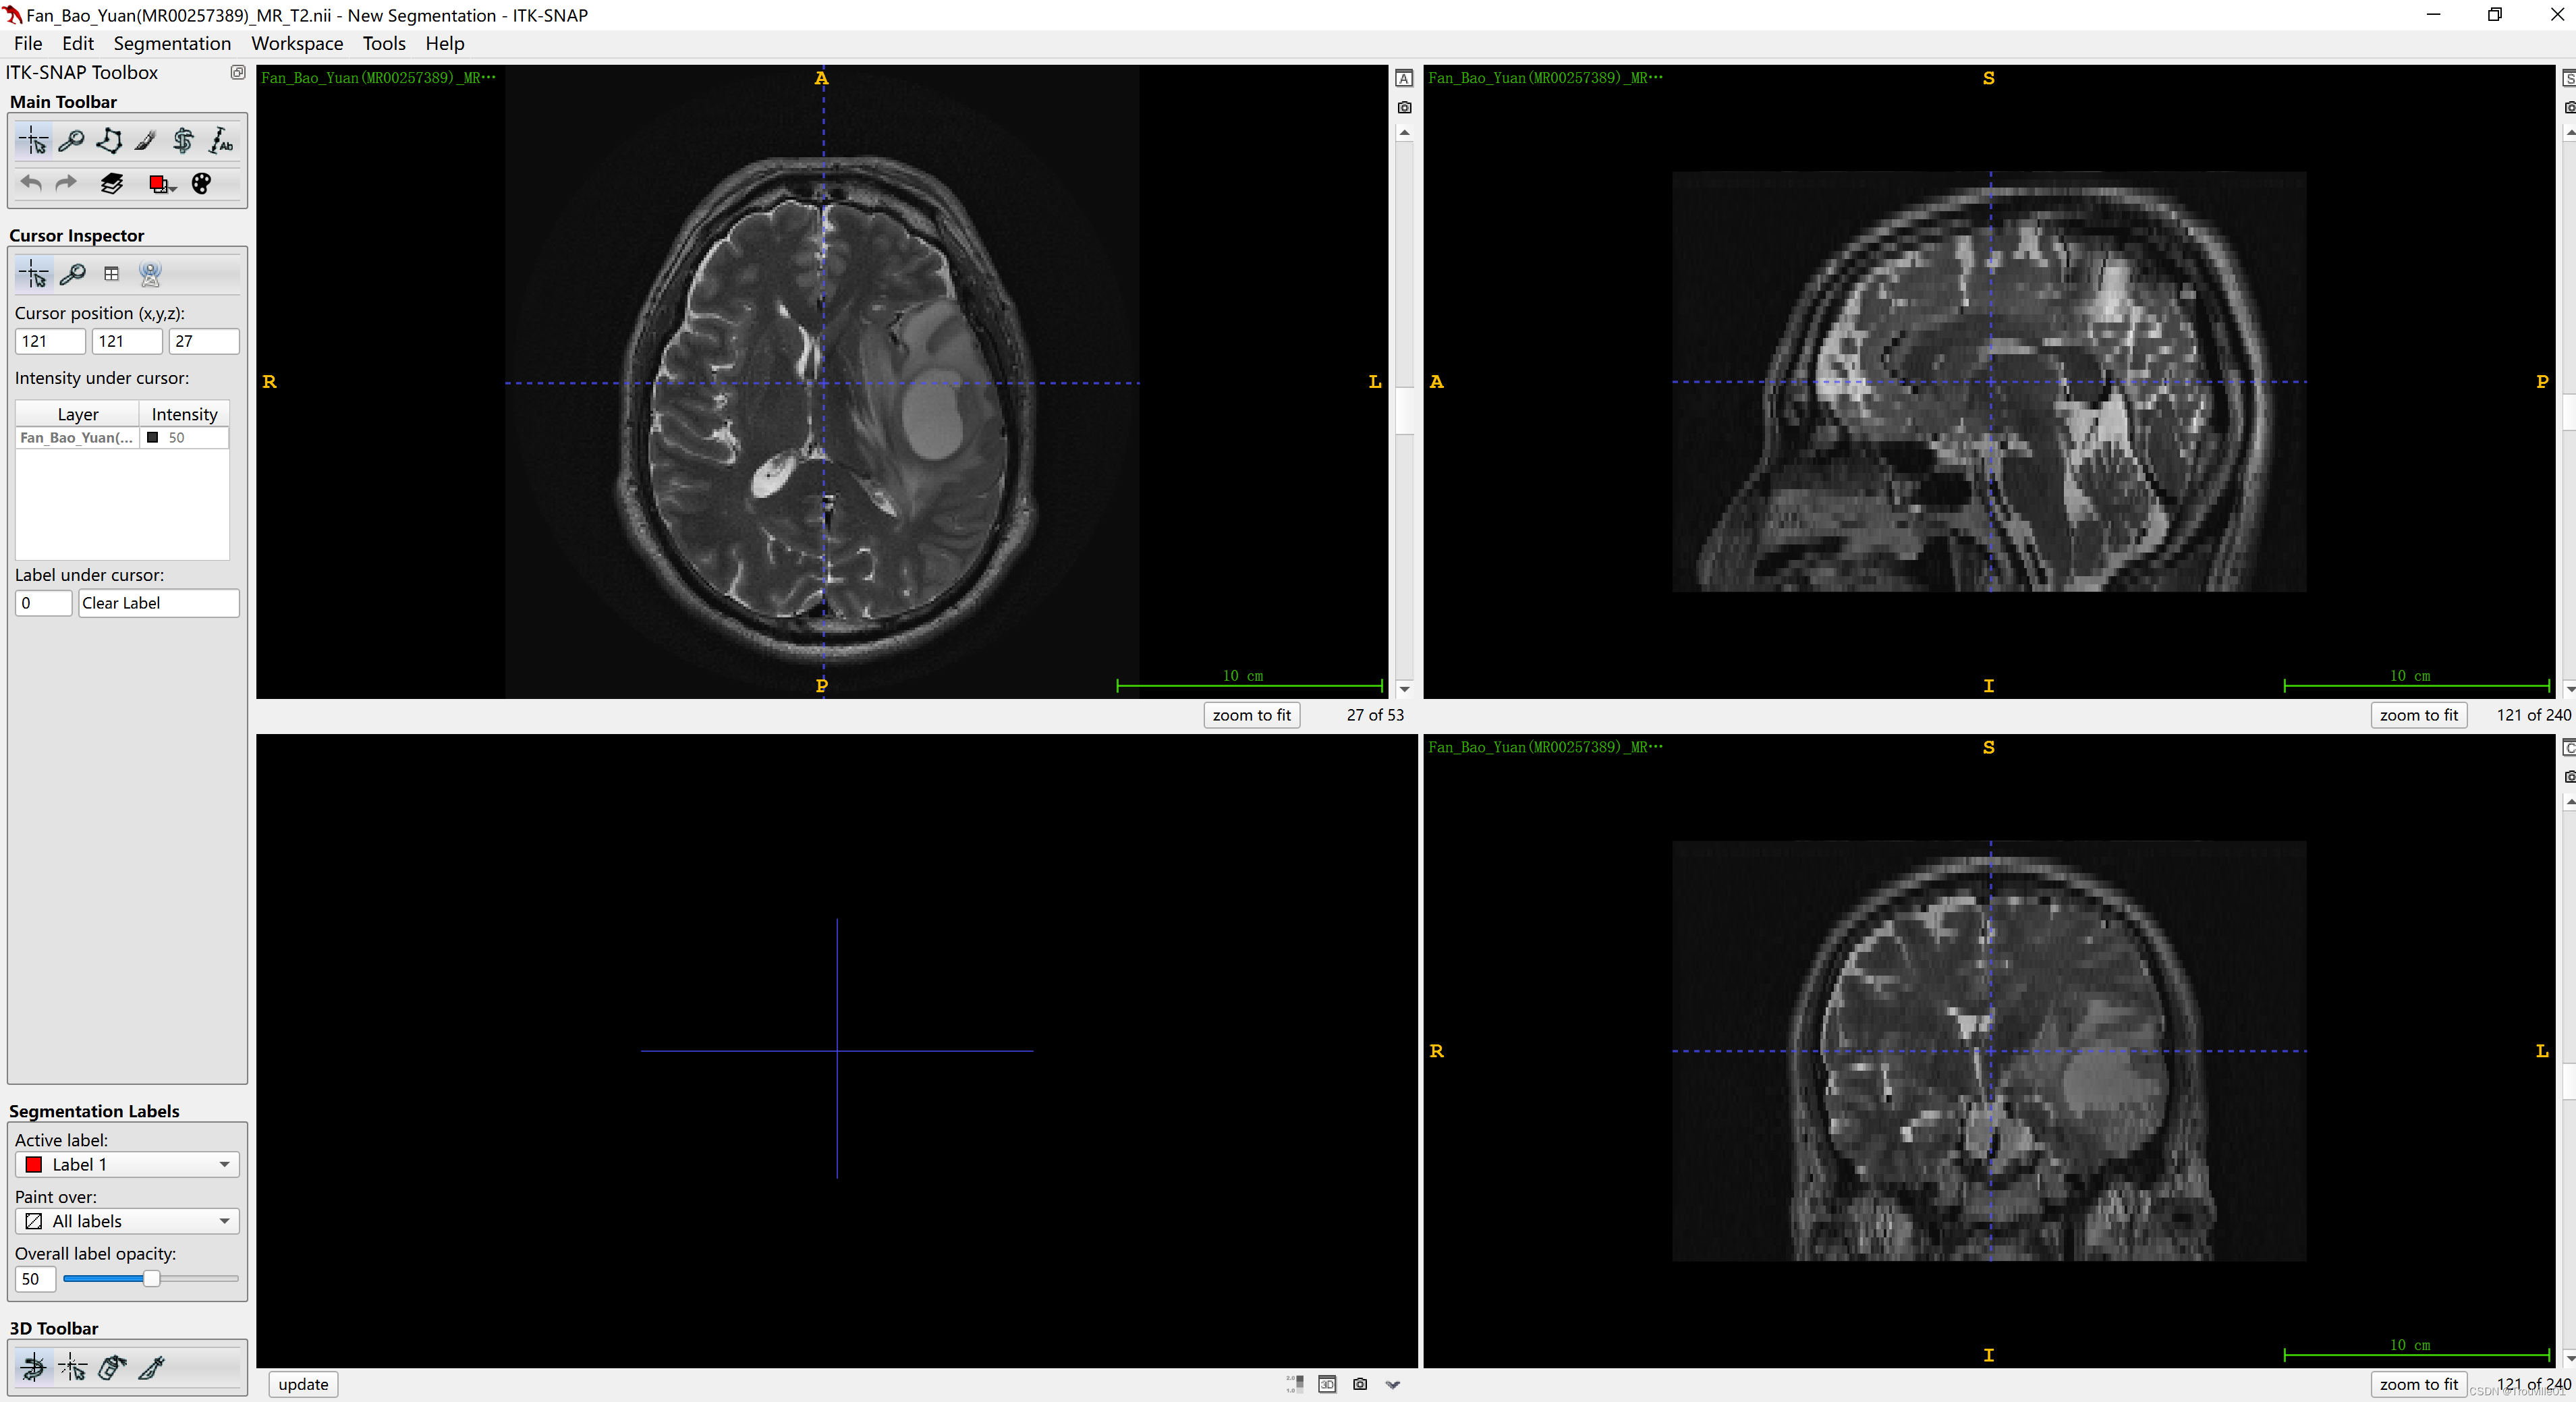

首先,确定你想要配准到的模态,比如,你想将T1W的序列配准到T2W序列上,这样可以使用T2W的标注ROI。那你需要首先打开T2W作为fix_image,然后再打开T1W作为moving_image,注意顺序不能错,如下图:

1.打开T2W